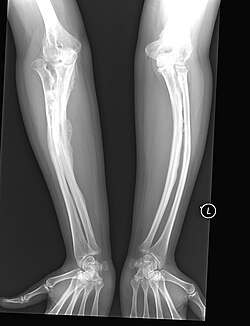

Betroffene dieses Typs neigen zum seltenen Phänomen des sogenannten hyperplastischen Kallus (Callus luxurians), einer spontan überschießenden Kallusbildung ohne eine hierfür übliche Fraktur mit anschließender Verknöcherung. Durch Einlagerung von Calciumsalzen in die bindegewebigen Strukturen (Syndesmosen) zwischen den beiden Unterarmknochen Elle und Speiche sowie den Unterschenkelknochen Schien- und Wadenbein (Calcifizierung der Membranae interosseae antebrachii et cruris) ist die Ein- und Auswärtsdrehung (Pronation/Supination) des Unterarms bzw. des Unterschenkels der Betroffenen erheblich blockiert, was zur klinischen Differentialdiagnose hilfreich ist, sofern die Bewegungseinschränkungen nicht auf Deformierungen der entsprechenden Knochen oder Gelenke beruhen.

Osteogenesis Imperfecta Type V in Adult | Eigenes Werk | ShakataGaNai | Datei:XrayOITypeV-Audult.jpg |